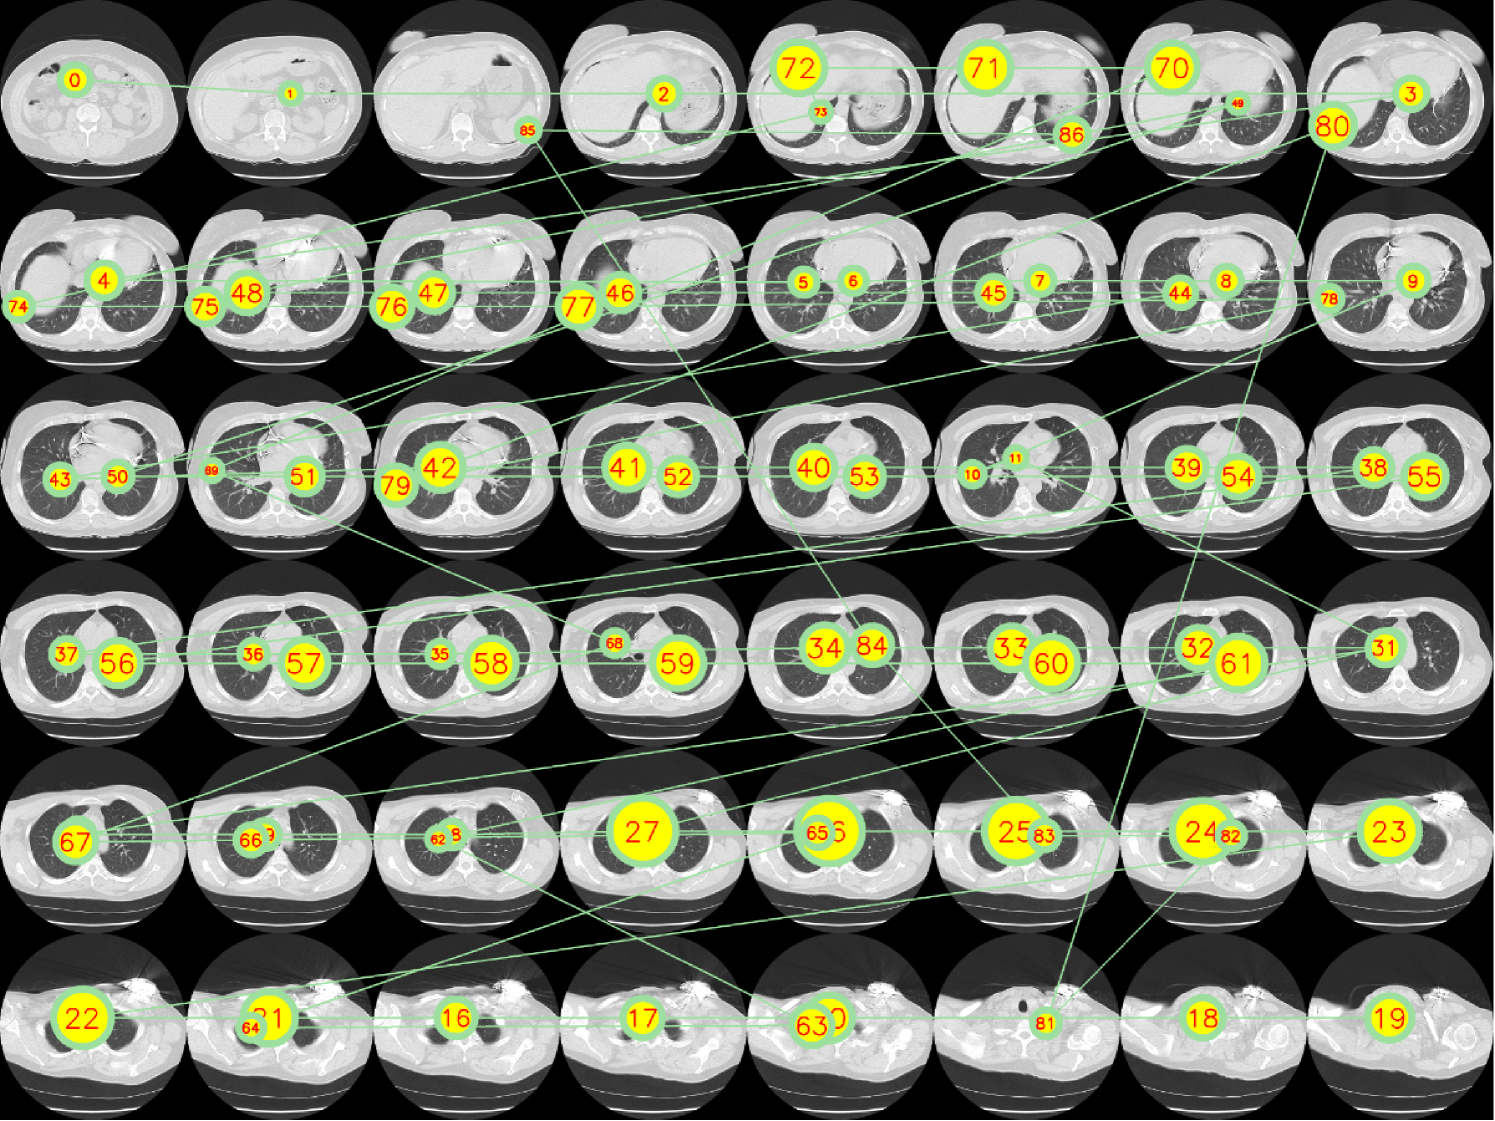

Refer to caption

Figure III: Illustration of fixation sequence across sequential CT slices, following a left-to-right and top-to-bottom order. The fixation start from 00 in the top left corner. The numbered annotations indicate the order of fixation points. In this figure, we observe the radiologist’s systematic viewing pattern: first scanning through all slices before returning to central regions for detailed examination. This navigation pattern is also demonstrated in Fig. IV. We suggest the readers to watch vis_gt.mp4 to see the animated version of this figure.

Figure IV: Visualization of temporal navigation patterns from the gaze data in Fig. III. The scanpath reveals that the radiologist follows a systematic approach: first traversing from start to end slices, then returning to central regions for detailed examination.

We visualize a CT volume with its eye tracking data from an alternative point of view, showing all scanpaths across slices in Fig. III and temporal navigation patterns in a line chart in Fig. IV. To create Figs. III and IV, we select a CT volume such that its fixation sequence has only 48 unique slices (48 unique z values) to maintain the simplicity of the visualization. An animated video is provided, named vis_gt.mp4. The observed scanpath pattern demonstrates a natural progression from peripheral regions inward to areas of diagnostic significance. The timestamped report is: